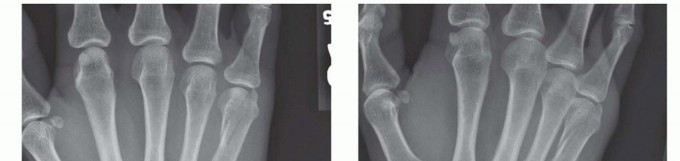

Standard radiographic imaging forms the cornerstone of diagnostic evaluation, requiring, at minimum, a dedicated posteroanterior (PA), a true lateral, and a pronated oblique view of the injured hand. The PA view is excellent for assessing coronal plane angulation and transverse displacement, though it notoriously underestimates sagittal plane deformity. The true lateral view is critical for quantifying apex-dorsal angulation, though overlapping metacarpal shadows can complicate interpretation. The pronated oblique view often provides the clearest visualization of the fracture profile and the degree of comminution.

With high-quality imaging in hand, the surgeon must engage in precise surgical templating. This involves selecting the optimal fixation modality—be it Kirschner wires, lag screws, dorsal plates, or intramedullary headless screws—based on the fracture's personality. For a long, oblique diaphyseal fracture where the fracture length is at least twice the diameter of the bone, interfragmentary lag screw fixation alone may provide sufficient stability. Conversely, a comminuted, unstable midshaft fracture with bone loss will necessitate a rigid dorsal locking plate utilized in a bridging construct.

Clinical & Radiographic Imaging Archive